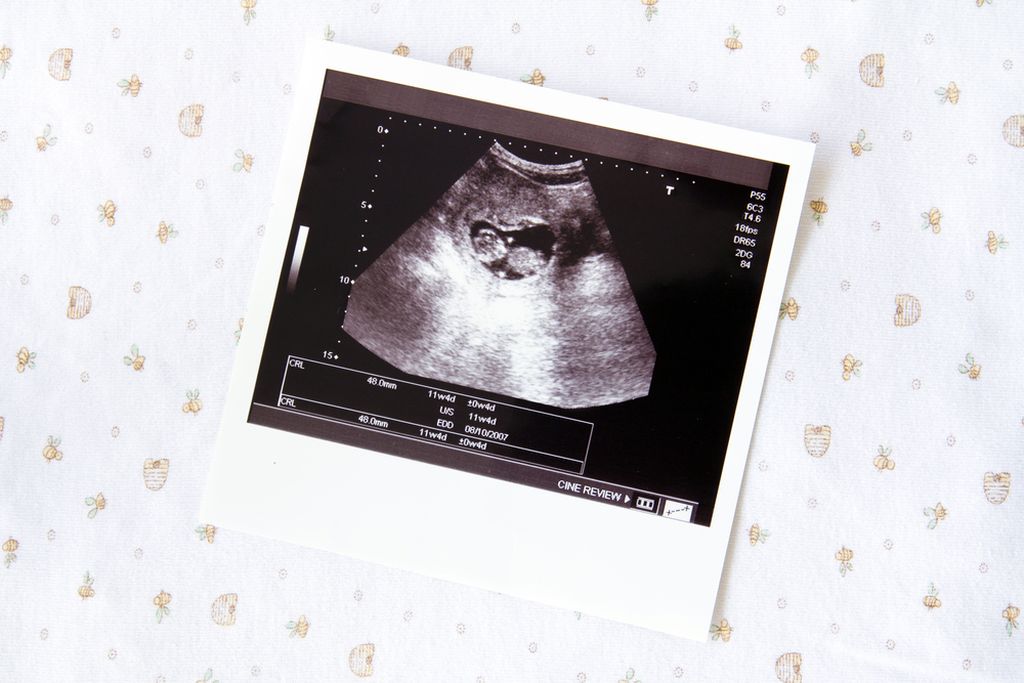

Δεν ήξερα ότι είμαι έγκυος! Μήπως δεν έπρεπε να…

Ένα χάπι για τον πονοκέφαλο ή για τον πονόδοντο. Μια γρίπη. Κοινά περιστατικά, που ωστόσο συμβαίνουν χωρίς να ξέρουμε ότι περιμένουμε μωρό. Τι επιπτώσεις μπορεί να έχουν;

Η είδηση έρχεται ξαφνικά. Το τεστ εγκυμοσύνης βγήκε θετικό. Συμβαίνουν αυτά. Να, όμως, που θυμόμαστε εκείνη την ημέρα που πήραμε τα χάπια για τον πονοκέφαλο, φάγαμε εκείνο το παράξενο φαγητό με το ωμό κρέας, πήγαμε στον οδοντίατρο για εκείνο το σφράγισμα. Είχαμε ήδη συλλάβει το μωρό τότε; Οι αμφιβολίες μας κατακλύζουν και η χαρά γίνονται εφιάλτης. Υπάρχει πράγματι λόγος να φοβόμαστε κάποια ανεπανόρθωτη ζημιά; Όλα εξαρτώνται από τη στιγμή κατά την οποία συμβαίνει το περιστατικό, λένε οι ειδικοί. Εάν συμβεί σε πολύ πρώιμη φάση, όταν το έμβρυο δεν έχει φθάσει ακόμη στη μήτρα και δεν έχει δημιουργήσει ζωτικές σχέσεις με τον οργανισμό της μητέρας δεν υπάρχει λόγος ανησυχίας. Συνήθως η ίδια η φύση φροντίζει να κάνει τις επιλογές της. Εάν το ωάριο υποστεί σοβαρή βλάβη προκαλείται αποβολή, που συχνά εμείς την αντιλαμβανόμαστε ως καθυστέρηση στον κύκλο. Διαφορετικά η κύηση συνεχίζεται. Είναι ο κανόνας του «όλα ή τίποτα». Αλλά και πάλι, παρότι ο κίνδυνος δεν πρέπει να υποτιμάται, ιδίως στην περίοδο από την τρίτη έως την εντεκάτη εβδομάδα κατά την οποία διαμορφώνονται τα όργανα του εμβρύου, το μυαλό μας δεν πρέπει να πηγαίνει στο χειρότερο. Εάν υποψιάζεστε ότι κάνατε κάτι επικίνδυνο χωρίς να ξέρετε ότι είστε έγκυος, καλό είναι άμεσα να πάρετε τη συμβουλή του γυναικολόγου σας, ο οποίος με τη βοήθεια των υπερήχων θα εντοπίσει με ακρίβεια το χρόνο έναρξης της κύησης και με αυτόν τον τρόπο θα εκτιμηθεί η πιθανότητα ύπαρξης επιπτώσεων, γιατί δεν συνεπάγονται κίνδυνο όλες οι περιπτώσεις. Επίσης, υπάρχουν εξειδικευμένα κέντρα στα μεγάλα δημόσια νοσοκομεία, που καθορίζουν τον κίνδυνο βλαβών του εμβρύου, αν εκτεθεί η μητέρα σε κάποιο βλαπτικό παράγοντα. Πόσο επικίνδυνα είναι τα φάρμακα; Έχει αποδειχτεί ότι τα φάρμακα ευρείας χρήσης είναι τα λιγότερο επικίνδυνα. Για παράδειγμα, τα πιο κοινά φάρμακα για τη γρίπη, τον πονόδοντο ή τον πονοκέφαλο, όπως αυτά που έχουν βάση το ακετυλοσαλικιλικό οξύ, την παρακεταμόλη ή τα αντιφλεγμονώδη, δεν προκαλούν βλάβες στο έμβρυο κατά τις πρώτες εβδομάδες της κύησης. Ακόμη και ορισμένα αντιβιοτικά, όπως η αμοξυσιλίνη και οι πενικιλίνες, δεν έχουν παρενέργειες για το μικρό. Αυτό βέβαια δεν σημαίνει ότι μπορούμε να παίρνουμε ανεξέλεγκτα φάρμακα, κυρίως εάν θέλουμε να συλλάβουμε παιδί. Τα πιο επικίνδυνα είναι τα φάρμακα κατά της επιληψίας, τα αντικαταθλιπτικά, η βιταμίνη Α σε πολύ μεγάλες δόσεις, που χορηγείται για ορισμένες δερματικές παθήσεις. Κίνδυνος από ακτίνες Χ Οι ακτινογραφίες προκαλούν μεγάλο φόβο, αλλά με εξαίρεση την ακτινογραφία στην κοιλιά, σε οποιαδήποτε άλλη περιοχή του σώματος της μαμάς, ακόμη και στα δόντια, δεν προκαλούν βλάβη στο έμβρυο. Αντίθετα, οι ακτινογραφίες στην κοιλιά έχουν σοβαρές συνέπειες και μόνο πολύ ακριβείς εξετάσεις μπορούν να διαπιστώσουν εάν έχει προκληθεί βλάβη. Ακόμη και για την αξονική τομογραφία χρειάζεται προσοχή. Είναι μια εξέταση που συνήθως περιλαμβάνει πολλές ακτινογραφίες μερικές από τις οποίες μπορεί να αφορούν την περιοχή της κοιλιάς. Στον οδοντίατρο χωρίς φόβο Έχει αποδειχτεί ότι τα μείγματα που χρησιμοποιούνται για τα σφραγίσματα δεν προκαλούν βλάβη στο παιδί. Αυτό ισχύει ακόμη και για την αναισθησία, καθώς οι ουσίες που χρησιμοποιούνται είναι πολύ ελαφρές και δεν επηρεάζουν την κύηση. Σημαντική είναι η αποφυγή της αδρεναλίνης κατά την αναισθησία, γεγονός που γνωρίζουν βέβαια οι οδοντίατροι. Αντίθετα, μπορεί να αποδειχτεί επικίνδυνη η παραμέληση της στοματικής υγιεινής, τόσο λόγω της βλάβης στο σμάλτο των δοντιών όσο και λόγω των βακτηρίων των ούλων που εισέρχονται στο αίμα και δημιουργούν προδιάθεση για πρόωρο τοκετό. Ποιος κοινός ιός; Εκτός από την ερυθρά, οι άλλες κλασικές μολυσματικές ασθένειες, από την ιλαρά έως την ανεμοβλογιά (που είναι επικίνδυνη μόνο κατά το τελευταίο τρίμηνο της κύησης γιατί μπορεί να μεταδοθεί στο παιδί στη διάρκεια του τοκετού), δεν δημιουργούν σοβαρούς κινδύνους. Τα βακτήρια της γρίπης ή άλλων εποχιακών νόσων, της ωτίτιδας ή της αμυγδαλίτιδας, συνήθως δεν βλάπτουν το έμβρυο. Όλα βέβαια εξαρτώνται από τη φάση της κύησης. Άλλη περίπτωση που προκαλεί μεγάλο φόβο είναι η τοξοπλάσμωση, μια λοίμωξη που μπορεί να μεταδοθεί από ωμό κρέας, φρούτα και λαχανικά που δεν πλύθηκαν καλά. Εάν η μέλλουσα μαμά υποψιάζεται ότι βρέθηκε σε επικίνδυνη κατάσταση καλό είναι να κάνει αμέσως εξετάσεις για τις ανοσοσφαιρίνες (ΙgG, IgA, IgM). Αλλά, ακόμη κι αν βγουν θετικές, δεν υπάρχει λόγος πανικού. Σήμερα, μόνο στο 2,5 τοις χιλίοις η λοίμωξη μεταδίδεται στο παιδί και από αυτές τις περιπτώσεις μόνο στο ένα δέκατο αναπτύσσονται σοβαρές βλάβες. Συνήθως η τοξοπλάσμωση θεραπεύεται με αντιβιοτικό που επιτρέπει στις περισσότερες περιπτώσεις την καλύτερη έκβαση της εγκυμοσύνης. Η πιο σημαντική λοίμωξη από ιό, είναι αυτή από τον Κυτταρομεγαλοιό ή CMV. Είναι ένας ιός που όταν έρθει σε επαφή η μητέρα δεν δίνει ιδιαίτερα συμπτώματα, παρά μόνο την αίσθηση ενός ελαφρού κρυολογήματος, με καταρροή. Οι βλάβες όμως που μπορεί να προκαλέσει στο έμβρυο κατά το πρώτο τρίμηνο, είναι μεγάλες. Κυρίως προσβάλει την καρδιά και τον εγκέφαλο, με αποτέλεσμα να έχουμε μωρά μη συμβατά με τη ζωή και να χρειασθεί να κάνουμε διακοπή εγκυμοσύνης. Για το λόγο αυτό, είναι απαραίτητη η εξέταση για λοίμωξη από το CMV και δίδεται σε κάθε προγεννητικό έλεγχο. Δυστυχώς, η μητέρα δεν μπορεί να κάνει κάτι για να αποφύγει μια δυνητική λοίμωξη. Ερυθρά, η τρομερή Είναι η πιο επικίνδυνη περίπτωση. Εάν εκδηλωθεί κατά τους δύο πρώτους μήνες της εγκυμοσύνης μπορεί να έχει πολύ σοβαρές συνέπειες στο παιδί. Γι’ αυτό πρέπει να καταφύγετε αμέσως σε κάποιο εξειδικευμένο κέντρο ώστε να ακολουθήσετε τις καταλληλότερες προφυλάξεις. Εάν αντίθετα κάνατε επίτηδες προληπτικό εμβόλιο κατά της ερυθράς και μείνατε έγκυος πριν περάσει το διάστημα ασφαλείας των τριών μηνών, μην πανικοβληθείτε. Δεν έχει αποδειχτεί ότι το εμβόλιο μπορεί να προκαλέσει ζημιά στο έμβρυο. Τα εμβόλια Το αντιγριπικό δεν είναι επικίνδυνο γιατί στα εμβόλια χρησιμοποιούνται εξασθενημένοι ιοί, ωστόσο συνιστάται στις εγκύους μόνο σε ιδιαίτερες περιπτώσεις. Επικίνδυνα κατά τις πρώτες φάσεις της σύλληψης δεν θεωρούνται ούτε τα εμβόλια κατά της ηπατίτιδας Α και Β και ο αντιτετανικός ορός. Εάν λοιπόν έχετε κάνει κάποιο από αυτά τα εμβόλια, το μωρό δεν διατρέχει κανένα κίνδυνο. Με την συνεργασία της κας Μαρίας Παπαδοπούλου (μαιευτήρας – γυναικολόγος)